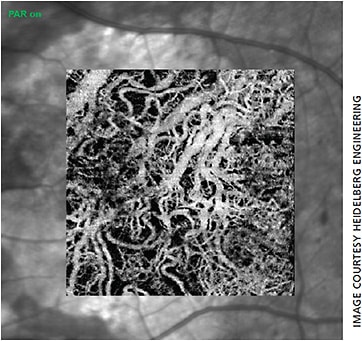

The Spectralis OCTA lets you comparatively track structure and function.

In September, Heidelberg Engineering announced that its Spectralis OCTA Module received FDA clearance, making it available here for new and existing upgradable diagnostic imaging devices.2 David M. Brown, MD, is a retina specialist at Retina Consultants of Houston, a practice that served as the principal investigator in the clinical trial for the FDA clearance of the technology. He reports that the OCTA Module has allowed him to comparatively track point-by-point references, from structural Spectralis OCTs gathered in his practice over the last seven years to new OCTAs taken with the OCTA Module. “This serial data analysis feature makes the Spectralis unique and indispensable.”

Heidelberg says the multimodal Spectralis offers the ability to combine OCTA with structural OCT, confocal scanning laser imaging and dye-based angiography in a single device.2 The 10° x 10° OCTA images have a lateral resolution of 5.7 µm/pixel to resolve the fine capillary network and an axial resolution of 3.9 µm/pixel for segmentation of the four histologically-validated retinal vascular plexuses.3 These include the nerve fiber layer plexus in addition to the superficial, intermediate and deep capillary plexuses.

“The superficial vascular complex is particularly useful for visualizing retinal vascular diseases such as diabetic retinopathy and retinal vein occlusion,” Dr. Brown says. “It allows you to easily see capillary dropout to assess why a patient’s acuity may be reduced and determine the visual prognosis.”

The deep vascular complex, which consists of the intermediate and deep capillary plexuses, is more finely tuned towards AMD. “Segmentation allows for viewing of the foveal avascular zone and macular capillaries that would otherwise be obscured by the superimposed layers with FA,” Dr. Brown says. “Although OCTA is improving logarithmically, the deeper layers are still prone to projection artifacts that make pathology harder to differentiate.” The Spectralis OCT offers TruTrack Active Eye Tracking, which prevents motion artifacts to ensure high quality images. Additionally, a projection artifact removal tool utilizes information from the superficial vascular plexus to remove artifacts via post processing for better views of the outer retina.4